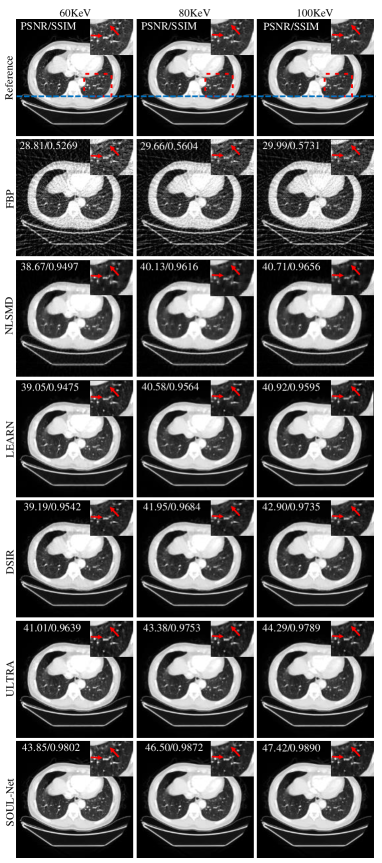

A typical thoracic case reconstructed using different methods is shown in Fig. 6. The lung window is used to show the details of the blood vessels. In the results of NLSMD, although noise and artifacts are well removed, most structural details in the lungs are blurred. LEARN and DSIR achieve better performance than NLSMD but still suffer from visible detail loss. ULTRA and SOUL-Net obtain promising results in terms of both artifact suppression and detail preservation. The ROI indicated by the red boxes in the first row of Fig. 6 is enlarged. It can be seen that the results of SOUL-Net maintain sharper edges and clearer structures, which can be better identified in the areas indicated by the red arrows and demonstrate the impressive potential in detail preservation of SOUL-Net. The SSIM and PSNR values of each reconstruction are given in the upper right of each subfigure of Fig.6. Our proposed method outperforms all other methods in terms of PSNR and SSIM.